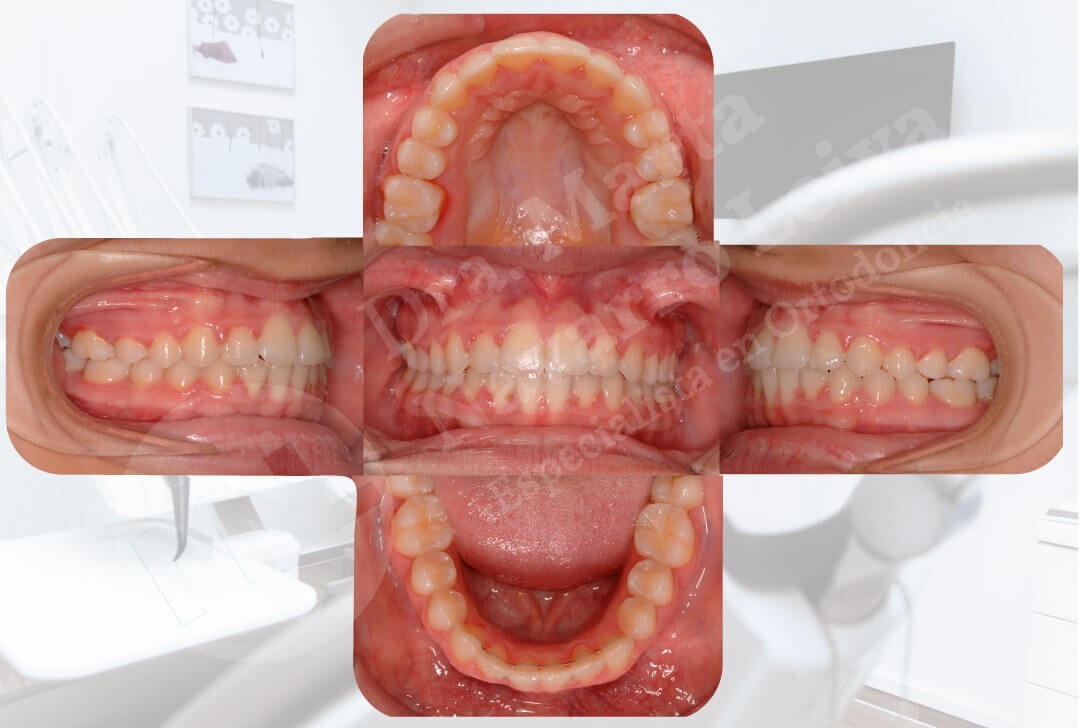

Deslice libremente el separador en cada uno de los casos para ver las diferencias entre maloclusión y resultado de ortodoncia.

Después

Después

Ver el resultado final en un paciente después de un tratamiento ortodóncico representa una gran satisfacción profesional y también personal.